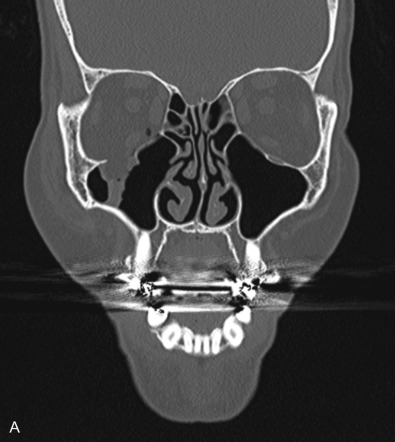

Thin-cut non-contrast CT of the orbits and face are the gold standard imaging modality for detecting orbital fractures. Cuts of 1–2 mm are generally recommended for adequate visualization, and the entire face should be imaged to assess for other associated facial injuries. Three-dimensional reconstructions may be helpful in assessing craniofacial fracture patterns following trauma. The orbital floor is best visualized on coronal and sagittal views, while the medial orbital wall is best seen on axial and coronal cuts. The sagittal view is particularly useful for assessment of the posterior ledge for orbital floor implant support. The coronal view provides good visualization of the orbital soft tissues and may be used to assess fat herniation or muscle entrapment. Rounding of the inferior rectus muscle has been associated with late enophthalmos if left untreated.